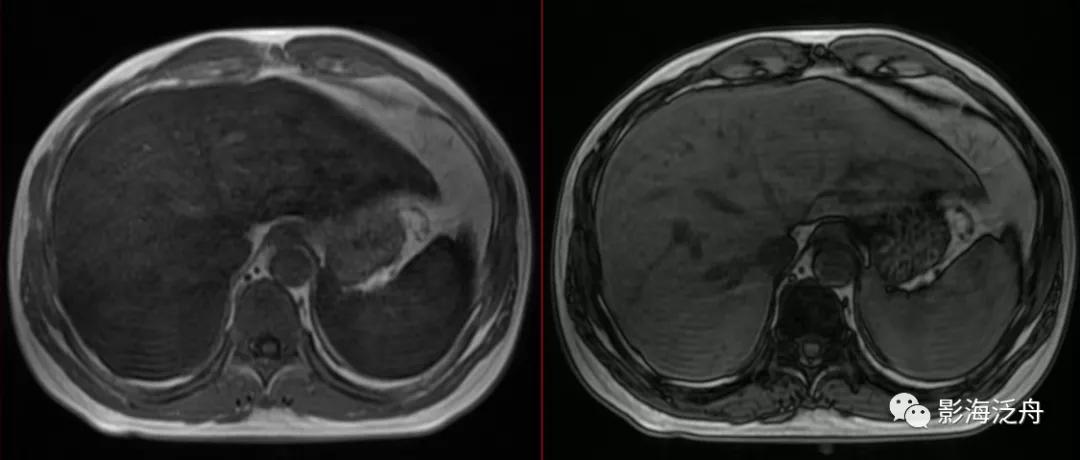

同一患者的MR平扫图像,T1WI同相位肝、脾实质信号较反相位明显减低,提示肝、脾铁沉积。

将铁沉积与脂肪肝的同反相位T1WI图像放在一起对比观察,可以看出两者的信号变化正好相反。

造成这种现象的原因是由于铁属于顺磁性物质,脏器内过多的铁沉积会缩短该脏器组织的T1和T2弛豫时间,T1弛豫时间的缩短会导致该脏器在T1WI序列上呈现高信号,而T2弛豫时间的缩短则会在T2WI序列上呈现明显低信号。